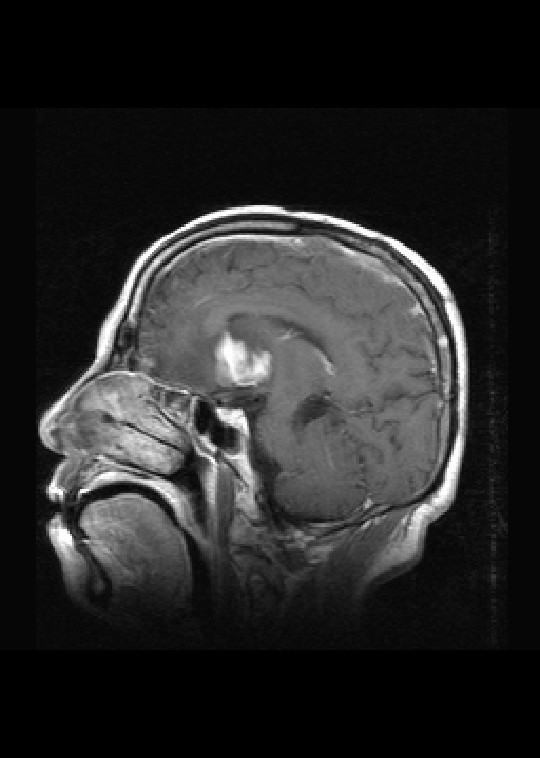

标题: MRI2527:脑部肿瘤,(病理结果:淋巴瘤)

(左额颞叶)非霍奇金淋巴瘤,b细胞性,弥漫性大b细胞型。免疫组化结果:cd45(lca) +,vimentin +,ck(ae1/ae3) -,ema -,cd3 -,cd20 +++,cd30 -,plap -,cd79a +,gfap -,alk -,s-100 -。

左侧基底节区病灶t1wi呈不均匀稍低信号,t2wi呈稍高信号,周围伴有水肿。增强扫描呈均匀团块样或者抱拳样明显强化,相邻的柔脑膜亦见线样强化。首先考虑淋巴瘤。可惜没有ct平扫,如果ct平扫病灶呈高密度,那么更支持pcnsl的诊断。

病理结果:(左额颞叶)非霍奇金淋巴瘤,b细胞性,弥漫性大b细胞型。免疫组化结果:cd45(lca) +,vimentin +,ck(ae1/ae3) -,ema -,cd3 -,cd20 +++,cd30 -,plap -,cd79a +,gfap -,alk -,s-100 -。

左侧基底节区病灶t1wi呈不均匀稍低信号,t2wi呈稍高信号,周围伴有水肿。增强扫描呈均匀团块样或者抱拳样明显强化,首先考虑淋巴瘤。